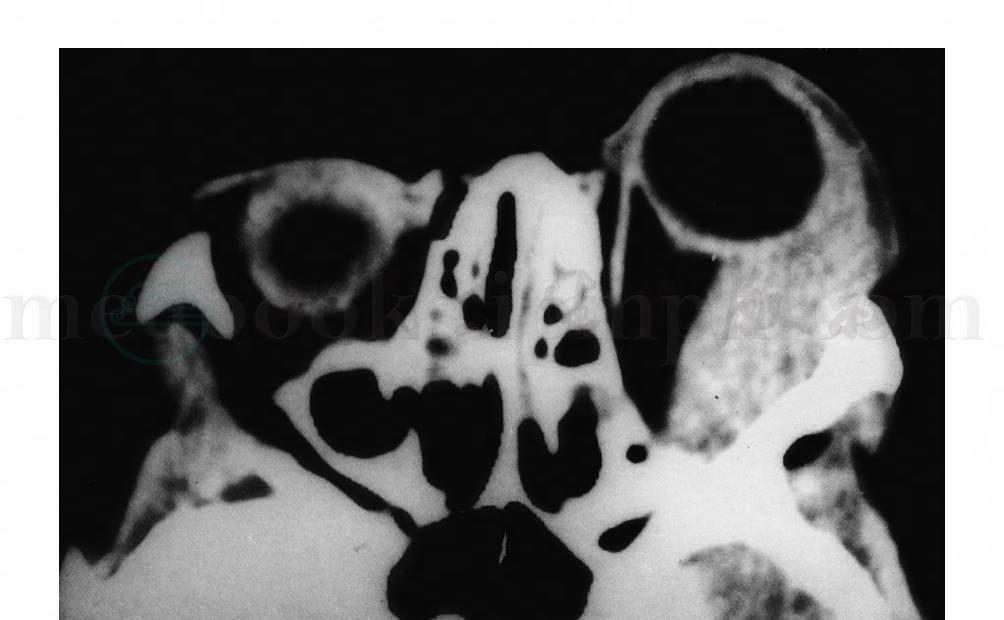

2.CT检查

CT扫描显示肿块形状不规则,边界不清,内密度不均匀,静脉注射造影剂后肿块明显增强,肿块充满眼眶,并向前沿巩膜生长,巩膜与肿瘤接触范围大,边界不清,形成所谓的铸造型,眼球明显前突(图2)。约2/3的病例有眶骨质破坏,大多数病例眶内侧壁、筛骨纸板破坏。肿瘤突进筛窦,肿瘤也可破坏眶底、眶外壁、眶顶,肿瘤向上颌窦、颞窝和颅内伸延。

图2 眼部横纹肌肉瘤CT图像显示左眼眶内外侧不规则肿块,与外直肌融合,眼球明显突出